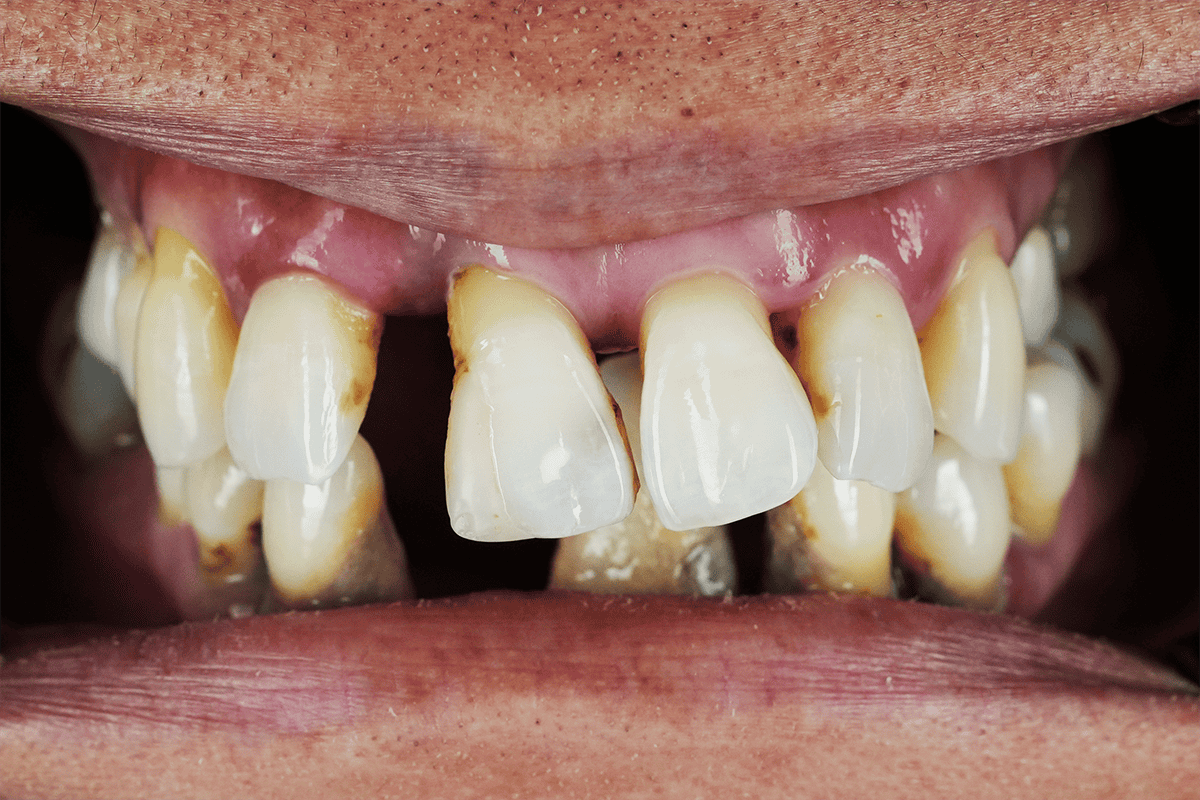

Periodontal disease

It is very important to seek professional dental care if you are experiencing any of the symptoms of periodontal disease, including:

- Red or swollen gums

- Pain while chewing

- Sore or bleeding gums

- Sensitive or loose teeth

- Receding gums

- Any change to the way your teeth fit together when you bite

Restoring smiles back to full functionality

At Advanced Dental Artistry, we have a passion for restoring smiles impacted by tooth loss or damage. Creating bespoke smiles and promoting genuine and compassionate care are two things we feel extremely strongly about. With over 60 years of combined experience, our team of cosmetic dentists take a personalised approach to each and every one of our patients. We have a range of treatments that are professionally designed and applied by our experienced team to ensure high quality results.